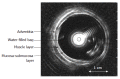

Methods: The evoked esophageal and duodenal contractile activity to standardized bag distension was assessed using a specialized ultrasound-based probe. Twelve type-1 diabetic patients with autonomic neuropathy and severe gastrointestinal symptoms and 12 healthy controls were studied. The geometry and biomechanical parameters (strain, tension/stress, and stiffness) were assessed.

Results: The diabetic patients had increased frequency of distension-induced contractions (6.0 +/- 0.6 vs 3.3 +/- 0.5, P < 0.001). This increased reactivity was correlated with the duration of the disease (P = 0.009). Impaired coordination of the contractile activity in diabetic patients was demonstrated as imbalance between the time required to evoke the first contraction at the distension site and proximal to it (1.5 +/- 0.6 vs 0.5 +/- 0.1, P = 0.03). The esophageal wall and especially the mucosa-submucosa layer had increased thickness in the patients (P < 0.001), and the longitudinal and radial compressive stretch was less in diabetics (P < 0.001). The esophageal and duodenal wall stiffness and circumferential deformation induced by the distensions were not affected in the patients (all P > 0.14).